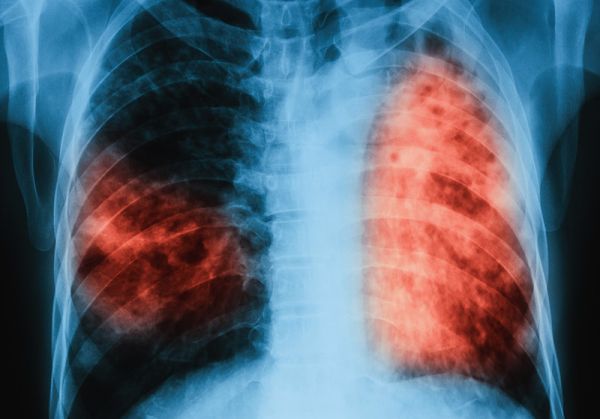

Запазва се тенденцията броят на мъжете да е два пъти по-голям от броя на жените, каза още зам. министър Йорданова. Над 75% от регистрираните пациенти са с туберкулоза на белия дроб. Броят на децата от 0 до 17 г. представлява между 9-10% от общия брой на туберкулозно болни в страната.

Заместник-министър Йорданова припомни, че туберкулозата е лечима напълно, стига да бъде открита навреме и лекувана. През 2017 г. са лекувани 47 пациенти с мутирезистентна форма на туберкулоза. Тяхното лечение е 70 пъти по-скъпо.

Лечението им е възможно благодарение на изградения по програмата, финансирана от Глобалния фонд за борба със СПИН и туберкулоза център в Габрово. В страната са извършени 38 хиляди микроскопски изследвания. 86% от хората, започнали терапия, са излекувани според критериите на СЗО. Лечението продължава от шест до осем месеца, а понякога до една година.